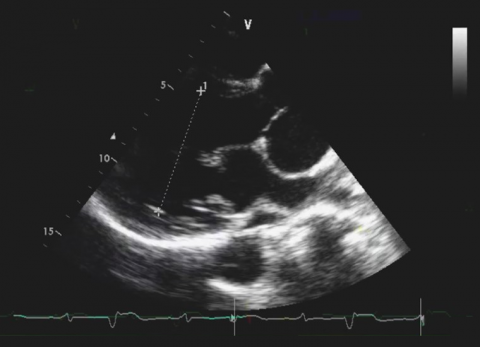

Pułapki Echokardiograficzne. Przypadek 39

dr n. med. Barbara Lichodziejewska

Pień płucny i jego zastawka. Tajemnicze obrazy.